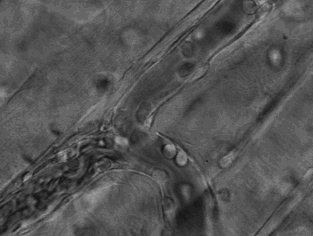

3.這張動(dòng)圖顯示的是嗜酸性粒細(xì)胞在趨化作用的“感知”下逐漸聚集到一只秀麗隱桿線(xiàn)蟲(chóng)周?chē)?duì)它進(jìn)行攻擊的過(guò)程。有“成千上萬(wàn)”的嗜酸粒細(xì)胞圍聚在線(xiàn)蟲(chóng)周?chē)?,就像一群螞蟻,善打“包圍?zhàn)”。